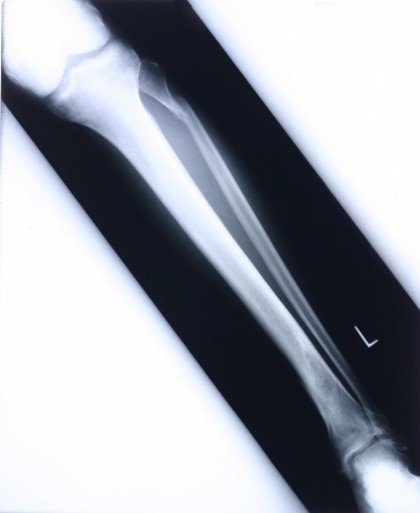

Studii imagistice:Modalitatile preferentiale pentru evaluarea condroblastoamelor sunt radiografia standard si computer tomografia sau rezonanta magnetica. Radiografiile pot rata condroblastoamele. Scanarea tomografica este utila in definirea eroziunilor corticale si a mineralizarii matricii.

Radiografia arata natura benigna, cu crestere lenta a condroblastoamelor. Tumorile apar in epifizele oaselor lungi in extremitatile inferioare. Sunt rotunde sau ovale, geografice, stralucitoare cu margini ascutite. Inelul exterior poate fi sclerotic, nonsclerotic sau incomplet sclerotic. Majoritatea leziunilor au 1-4 cm in diametru. 40% sunt limitate la epifiza, restul prezentind extindere. Condroblastoamele prezinta modele de mineralizare matriciala diferite. 40% sunt stralucitoare uniform iar 60% prezinta opacitate prin calcificari si septari.

Prin cresterea dimensiunilor, condroblastoamele se extind la metafiza si determina erodare endosteala, exteriorizarea cortexului subiacent si reactie periosteala.